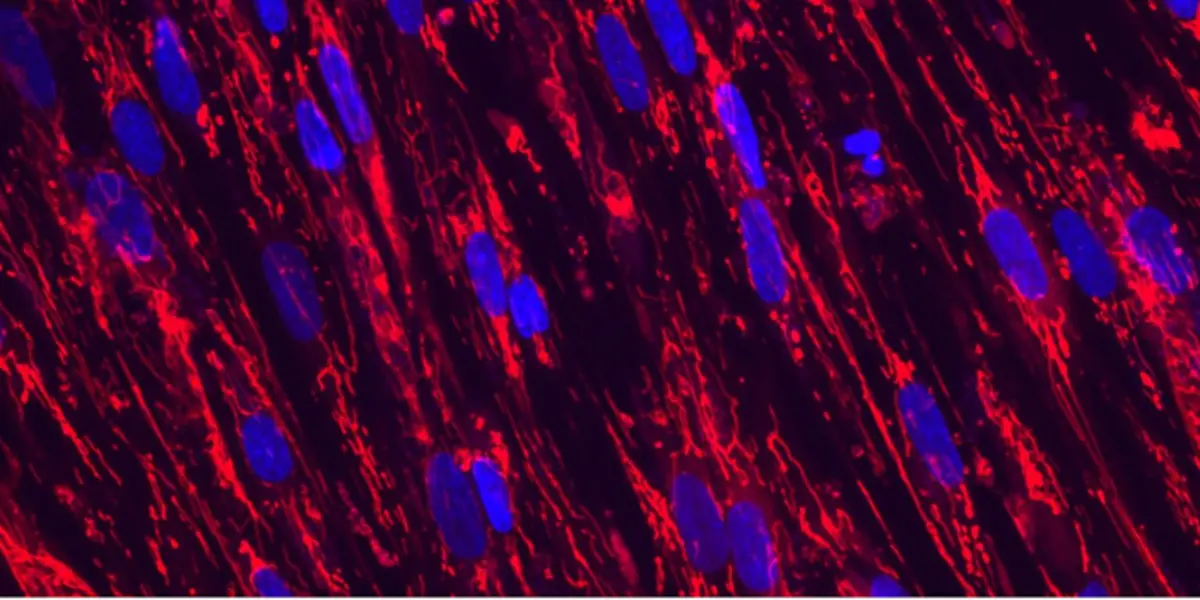

Skeletal Mitochondria

The mitochondrial network in cultured human skeletal muscle cells, courtesy of Ryan Hahn